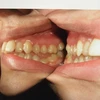

اعوجاج الأسنان